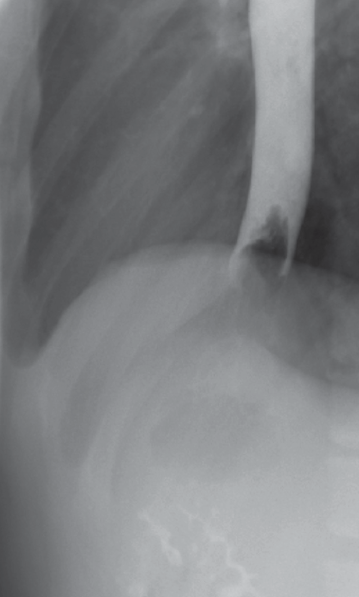

An esophagram done about 5 hours after the ingestion showed a foreign body in the distal esophagus with dilation of the proximal esophagus (Figure 1). Findings of a second esophagram done 17 hours after ingestion remained unchanged.

Figure 1. A foreign body in the distal esophagus with dilation of the proximal esophagus is apparent in this esophagram of a teenage boy with food impaction.